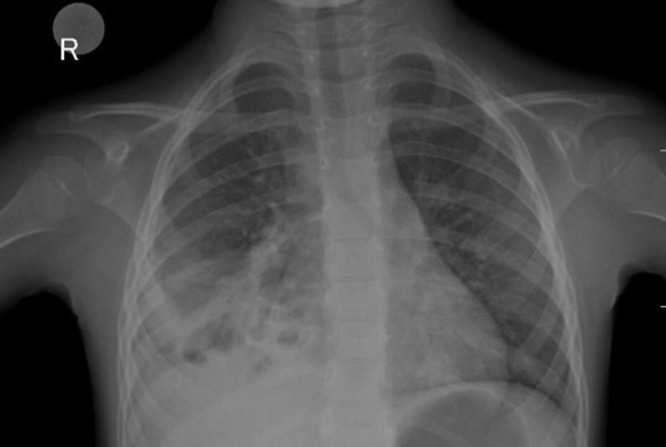

Methods: This case report presents the case of a 4 years and 5 months old patient diagnosed with invasive pneumococcal-associated pneumococcal infection in the context of SARS-COV2 infection.

Abstract Image